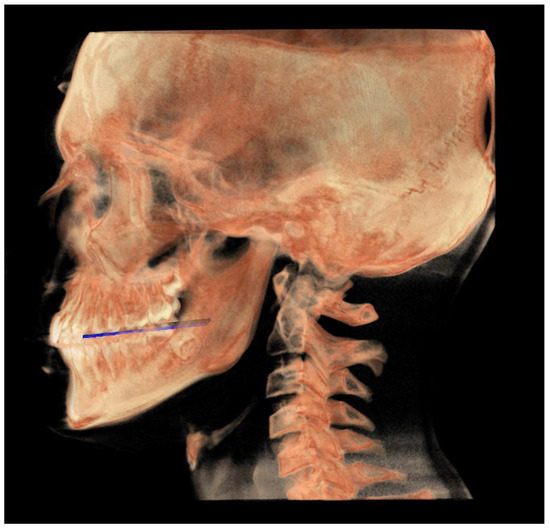

- The functional occlusal plane (FOP) (Figure 6) was identified by the posterior occlusal contact right side (rPoc), posterior occlusal contact left side (lPoc) and the middle point between the right and left anterior occlusal contact (mAoc). To adequately locate the mAoc, it is advisable to draw a line on the transversal view from the right mesial premolar contact to the left one to have a reference along which measure the distance.